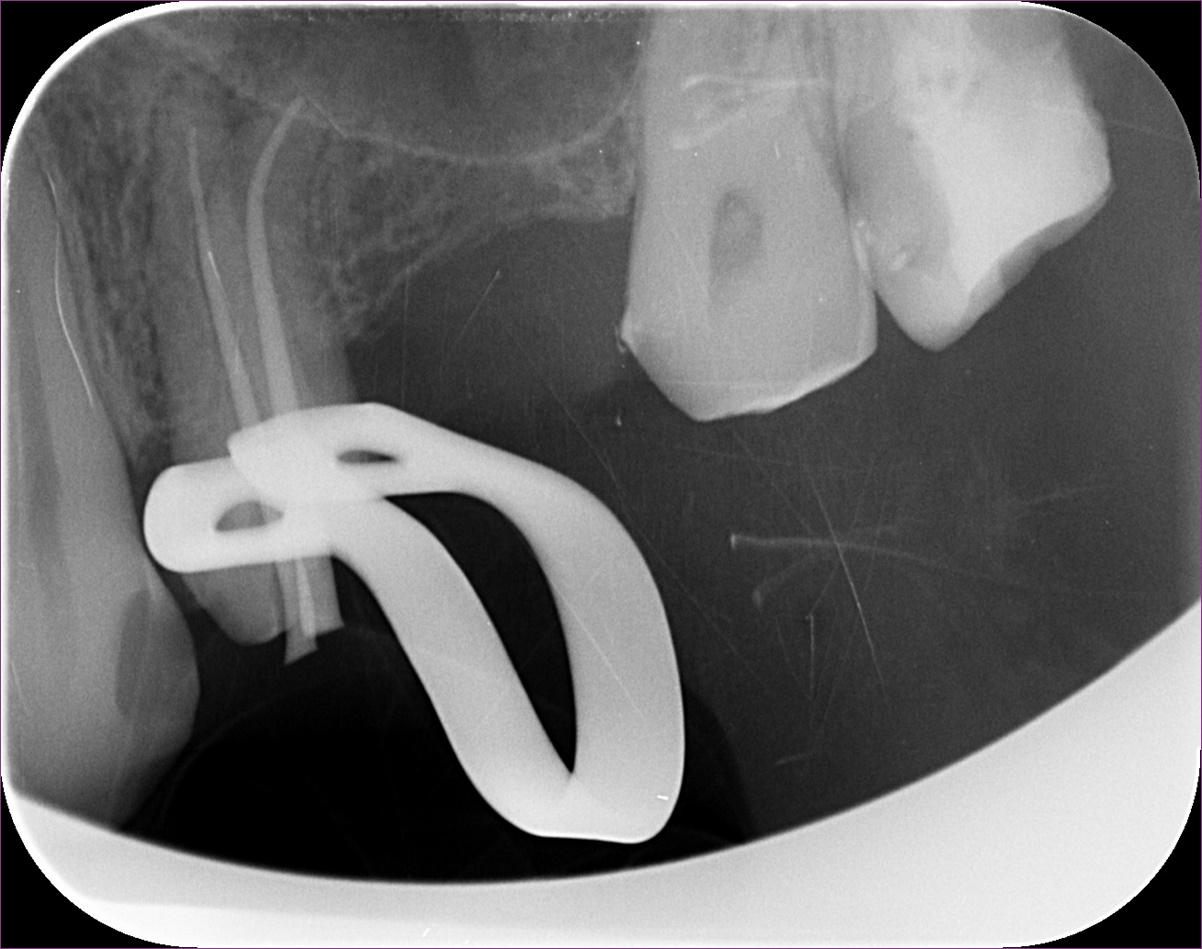

Ezen a képen látható a fog kontrollfelvétele. A gyökértömést követően a fogat üvegszálas-csapos megerősítéssel láttuk el, ezt követően pedig a kezelőorvos beragasztotta az elkészült hídpótlást.